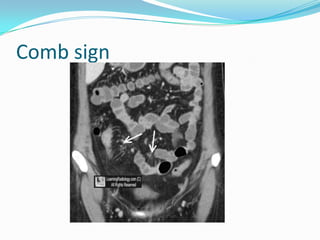

CT Enterography

The sensitivity - 82%

specificity - 89%

accuracy - 85%.

 Mural enhancement

 Mesenteric fat stranding

 The comb sign

 Pseudosacculations

Comb sign